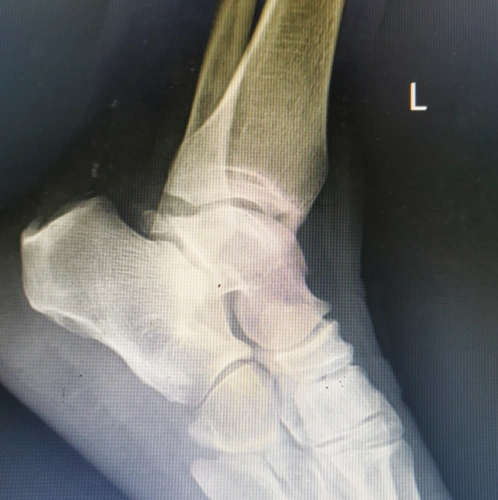

术前x线片显示跟骨增生骨刺明显.

左脚x光片显示跟骨刺呈红色.